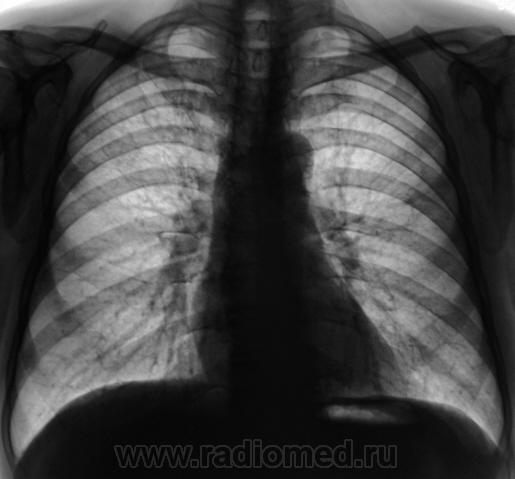

Пациент 4 месяца, по полной программе отлежал в областной конторе, ЦВК утвердило «инфильтративный». После выписки был направлен под надзор фтизиатра по месту жительства. Ниже иллюстрации после выписки.

Снимки сегодня.

Хорошая динамика, практически все рассосалось.

На мой взгляд на "семерке" еще дай-дай...